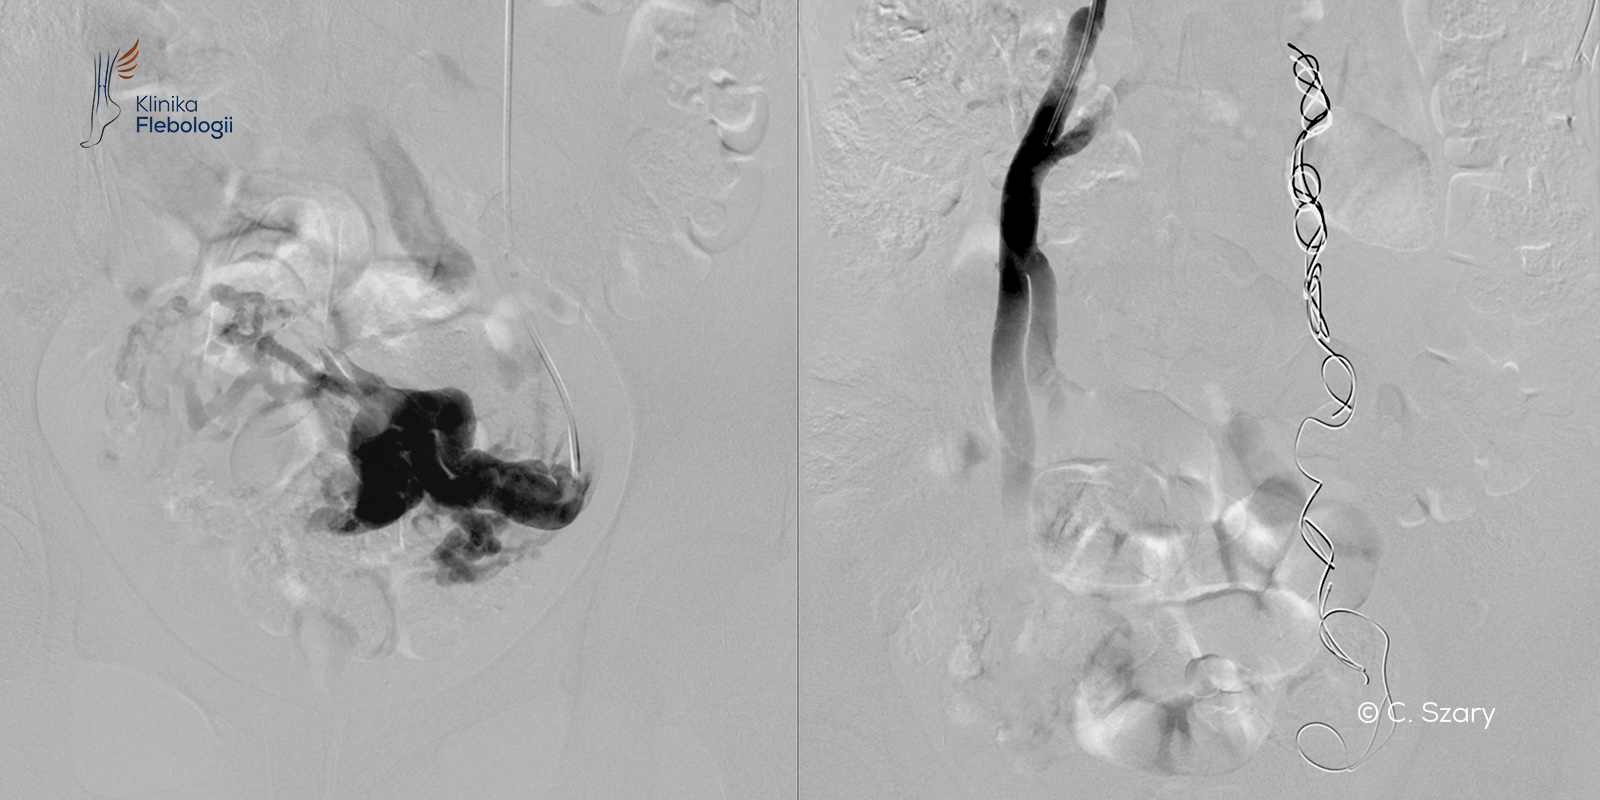

W przypadkach najtrudniejszych, gdy objawowej niewydolności żylnej miednicy towarzyszą żylaki okolic intymnych i nóg, stosujemy podejście kompleksowe. Polega ono na wyeliminowaniu przyczyny zastoju żylnego w miednicy małej (na drodze embolizacji żylnej, implementacji stentów żylnych czy zastosowaniu obliteracji chemicznej), a następnie wyleczeniu żylaków krocza, sromu i wreszcie szpecących poszerzeń żylnych na nogach (pajączków, poszerzonych żył siatkowatych i żylaków).

W pracowni hemodynamiki Szpitala Medicover stosujemy zdecydowanie najczęściej zabiegi małoinwazyjne przeprowadzane drogą wewnątrznaczyniową. Każdy zabieg wykonywany jest pod kontrolą sondy USG i cyfrowej aparatury angiograficznej (tworzony jest tzw. venogram).

Procedura embolizacji żylnej przeprowadzana jest w trybie 6-8 godzinnego przyjęcia do szpitala, zwykle bez konieczności stosowania znieczulenia ogólnego, jedynie w płytkiej sedacji. Pacjent jest przytomny i reaguje na polecenia lekarzy wydawane w czasie zabiegu.

czytaj więcejZabiegi z zakresu radiologii interwencyjnej są wyjątkowo skuteczne, wykonywane bez znieczulenia ogólnego, jedynie w płytkiej sedacji pod kontrolą anestezjologa. Dzięki stosowanej przez nas technice "sandwich" możemy bardzo precyzyjnie i bezboleśnie zamykać praktycznie wszystkie powstałe po ciążach żylaki.

czytaj więcejGłówne wskazania to: objawowa niewydolność żylna miednicy (tzw. zespół przekrwienia biernego miednicy); atypowe żylaki kończyn dolnych wynikające z niewydolności żylnej miednicy...